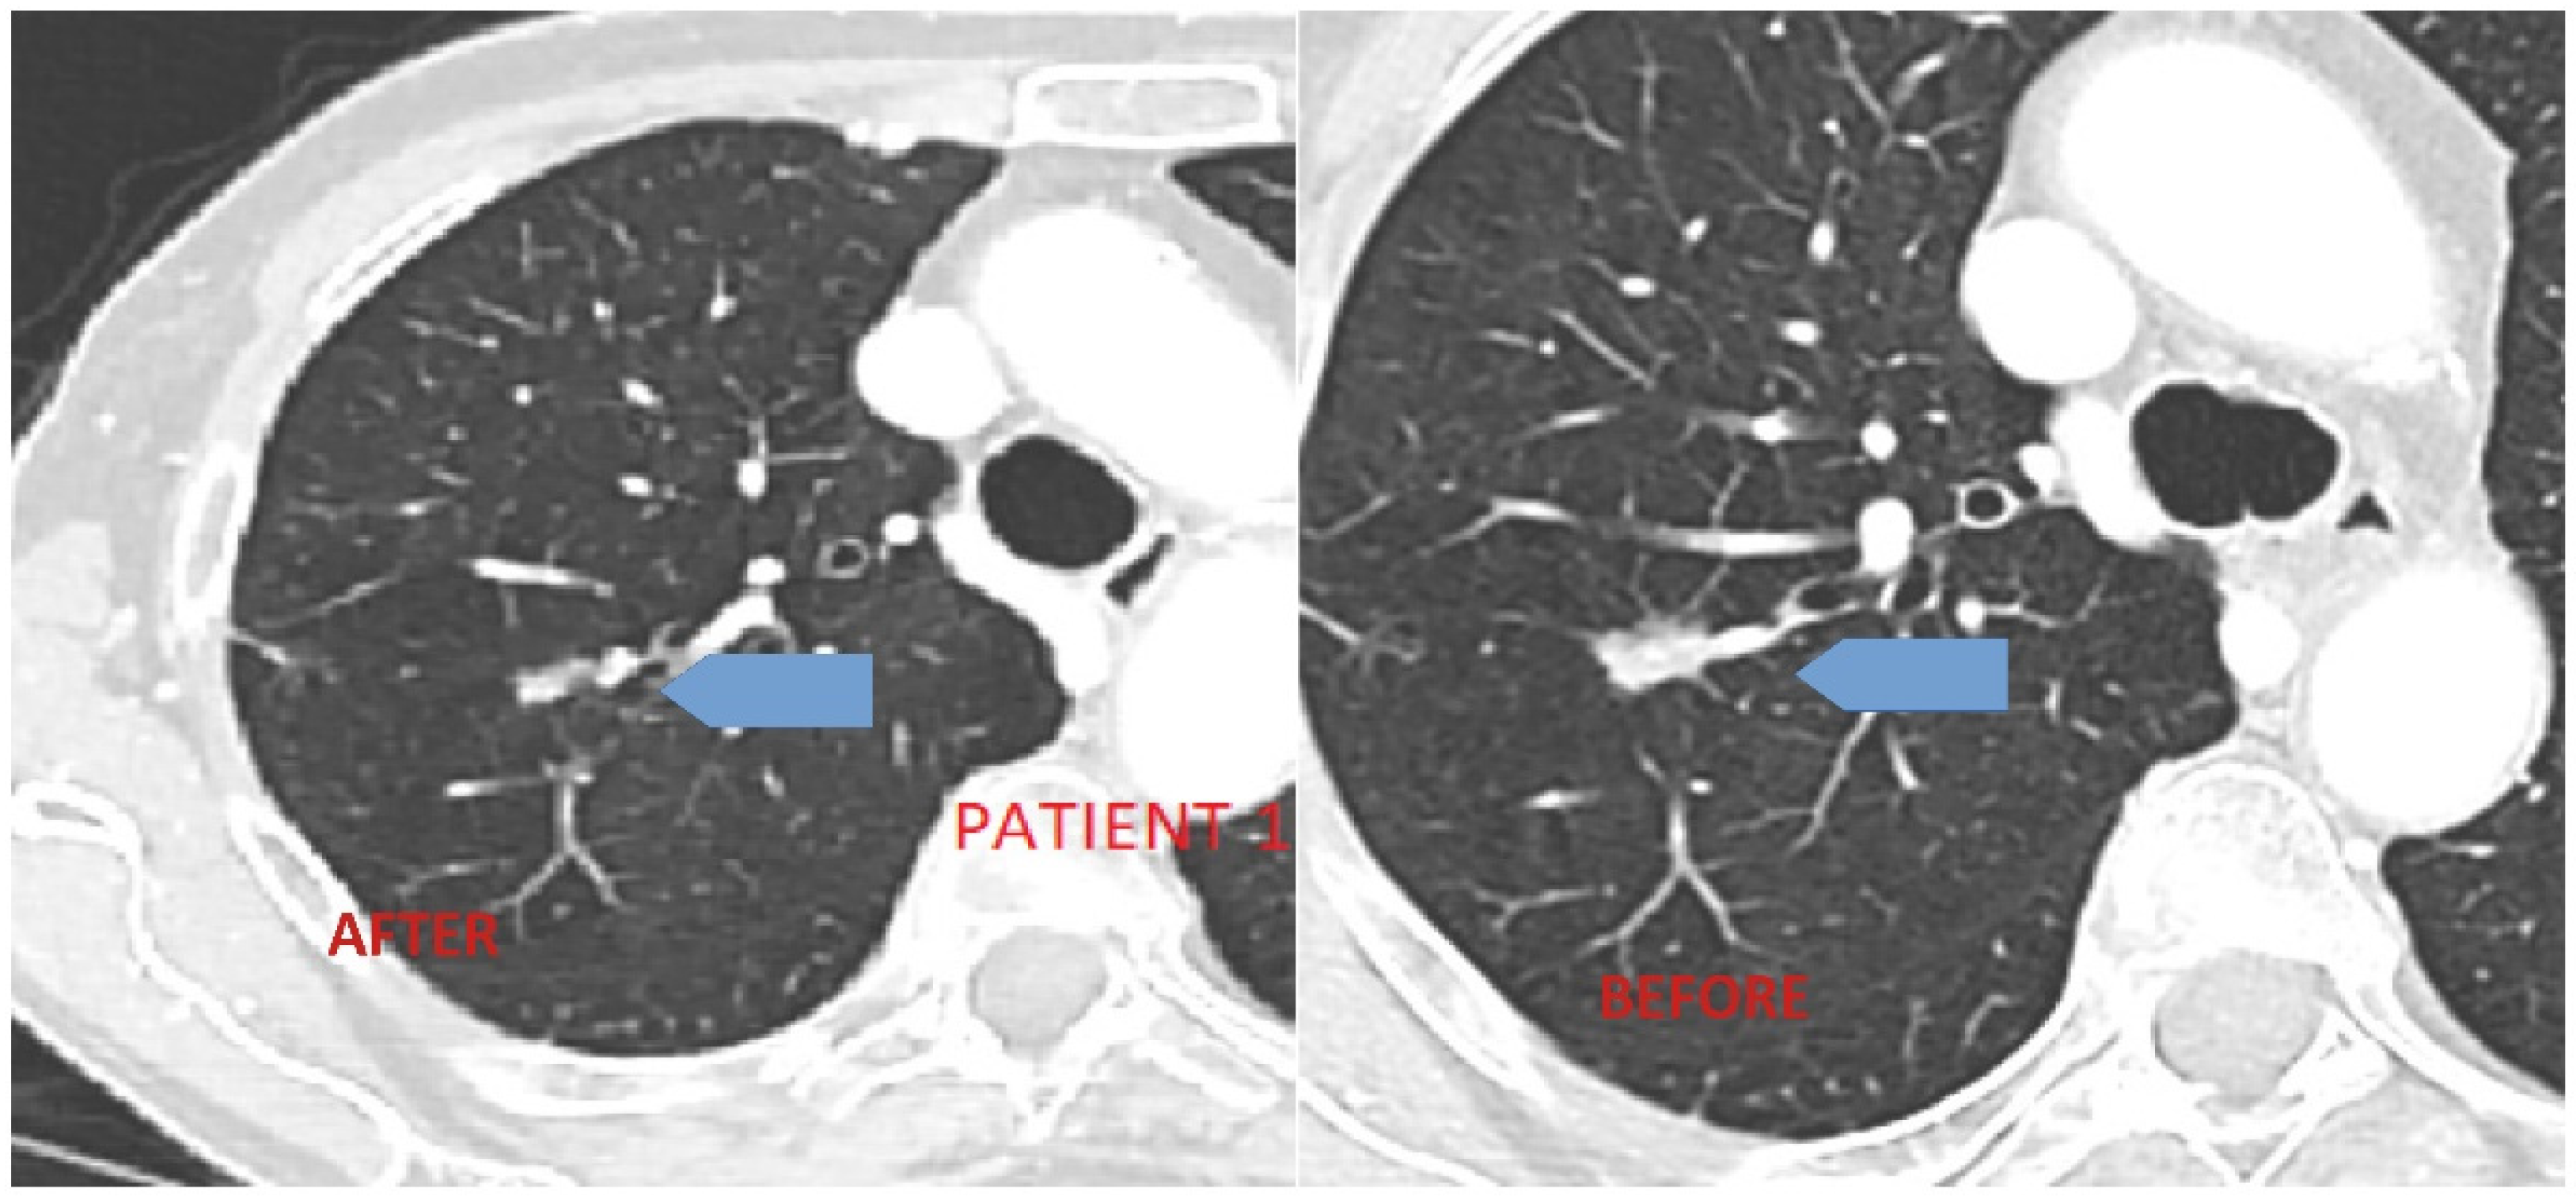

3.1. Case 1